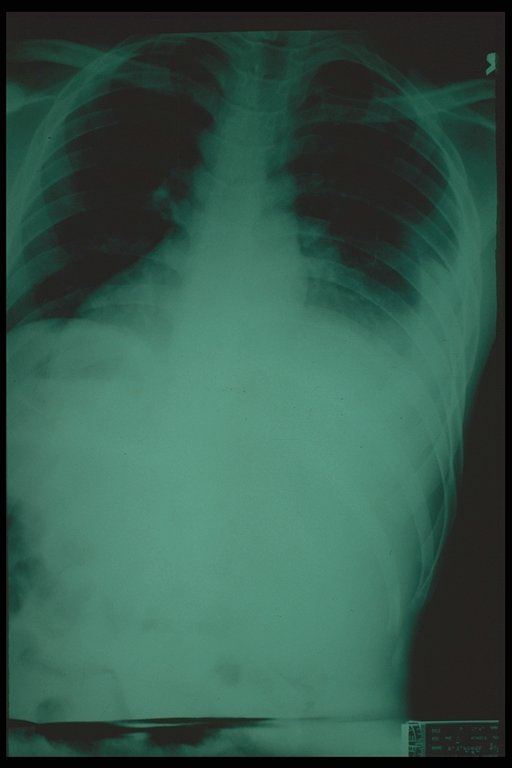

Multiple thoracoabdominal injury, haziness and blunting of costodiaphragmatic recess indicating the hemothorax.

Plain chest X-ray finding of ruptured diaphragm. The bowel gas pattern is noted in the right hemithorax